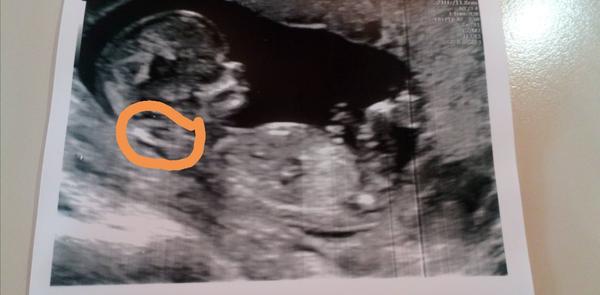

Sijove projasneni(nuchalni transluescence) je viz fotka to světlé v kroužku. To je to prosaknuti. Pokud Ti neudělají testy na screeningu na syndromy tak nevíš jestli má malý nějakou vrozenou vývojovou vadu. A hodnota NT je stejně dobrá do nějakých 2,5 pak by Tě mohli poslat na placený panorama test nebo na plodovku. Případně sem hoď fotku celého mimča kde půjde vidět vše. Takhle se těžko hádá když si sem dala jen část

@lilian2111 náš malý měl na prvním screeningu hraniční šíjové projasnění (2,5).. přišla jsem tam s tím že jsem 13+5, ale podle velikosti byl pozadu o 4 dny (což je super, mám ovulaci týden před ms), objednali mě na kontrolní ultrazvuk o týden a půl později a maličký už byl naprosto v pořádku. Takze i kdyby vám na prvním ultrazvuku něco řekli, tak nemějte strach, prcci z toho většinou vyrostou 🙂 Pošlu fotku soukromě, protože mi sem nejde přidat 🙂